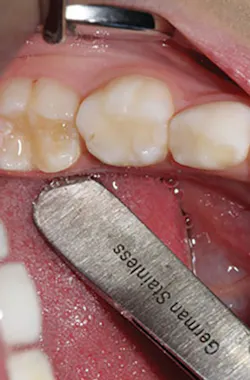

Cementation was then achieved as follows: Once satisfied with fit and occlusion, the prepared tooth was washed and dried but not desiccated. The NuSmile zirconia crown to be cemented was filled with cement (BioCem; NuSmile). Working time was approximately 60 seconds. The crown was set into the correct position. BioCem was photo cured with a tack cure of 10 seconds to the facial and 10 seconds to the palatal aspect. The cement was then cleaned interproximally using floss. Once all cement was removed, a final photo cure of 10 seconds to the facial and palatal was applied. One-month postoperative occlusal view and occlusion are pictured in Figures 4a and 4b.

Figures 4a and 4b: Final restoration